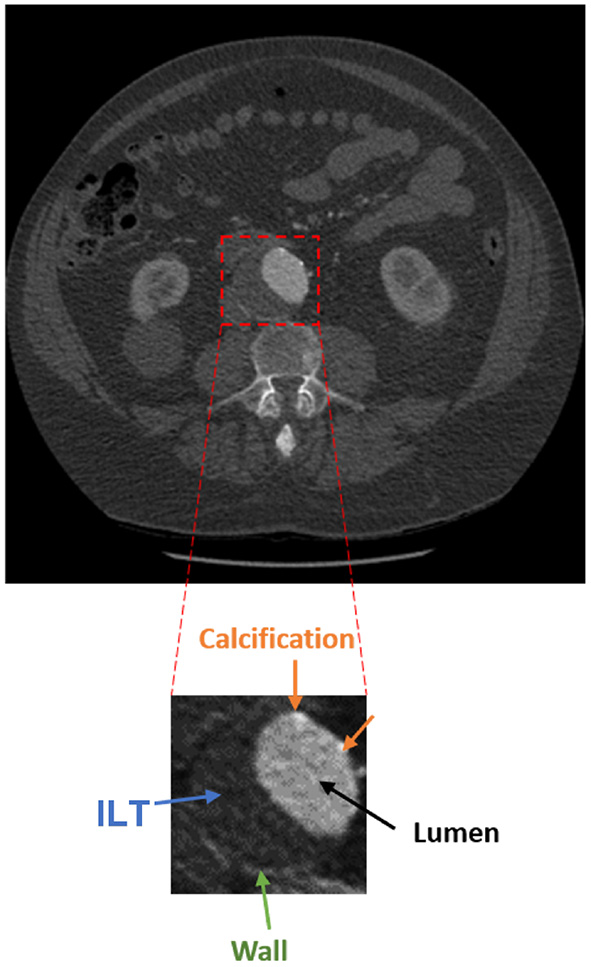

The presence of an aneurysm and its progression are normally assessed using CT imaging. Figure 1 shows an axial image from a CT scan of the abdomen of a patient. The aorta, a small fraction of the whole image, is located anteriorly to the spinal column and is composed of the wall, lumen, ILT, and calcification. The adoption of a three-dimensional assessment of the aorta is limited by the lack of standardized automated segmentation tools for the aorta, in particular for the aortic wall (6).

Figure 1

Axial acquisition of an abdominal CT scan showing an AAA. The aorta is a small fraction of the whole image and is composed of the lumen (black), ILT (blue), wall (green), and calcification (orange).